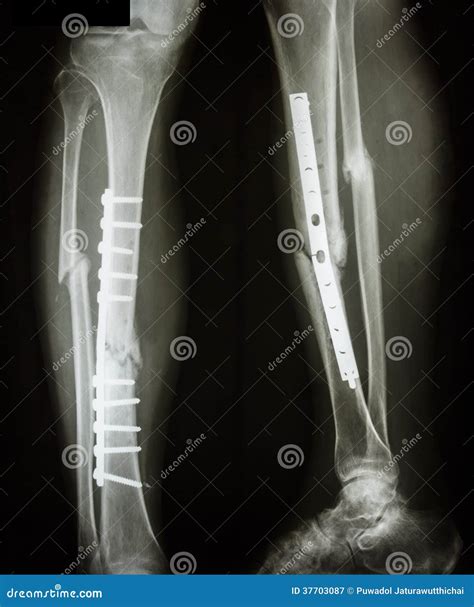

Treatment Options for a Broken Fibula and Tibia

The treatment for a fibula and tibia broken depends on the severity and type of fracture. Common treatment options include:

• Immobilization: Using a cast, splint, or brace to keep the bone in place while it heals.

• Surgery: In severe cases, surgery may be required to realign the bones and stabilize them with plates, screws, or rods.

Recovery and Rehabilitation

Recovery from a fibula and tibia broken can be a lengthy process, often taking several months. The rehabilitation phase is crucial for regaining full function of the leg. Key aspects of rehabilitation include: